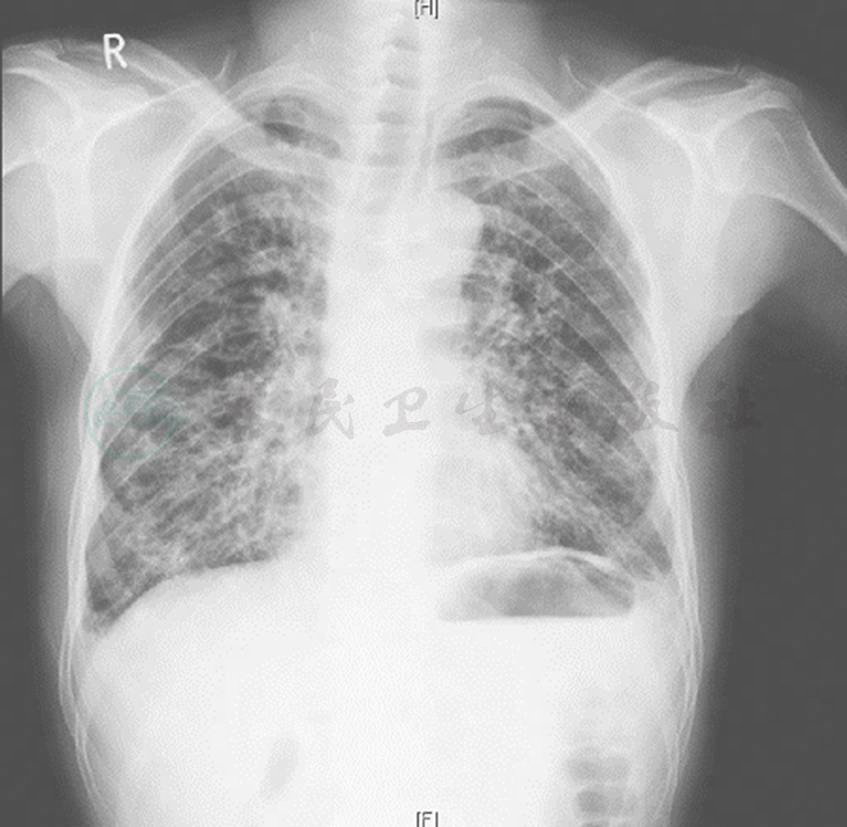

入院时X线胸片示双肺多发斑片、网格影,双侧肋膈角变钝(图2)。

图2 入院时X线胸片